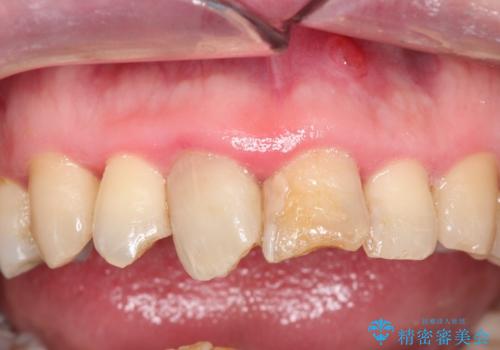

かけた前歯をきれいにしたい

- かけてしまった前歯をきれいにしたいとのことで来院されました。

レントゲンを撮影すると、根の神経の治療が必要なことがわかりました。

根管治療を行いセラミックを装着する計画としました。